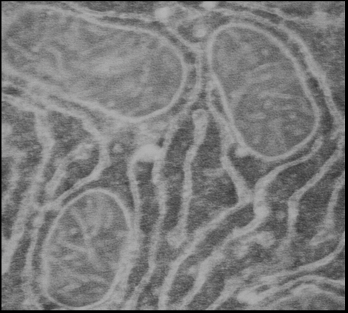

5.5 Электронная микроскопия МитоКАТФ

канала

5) Исследовать иммунолокализацию МитоКАТФ

канала на срезе гепатоцитов и кардиомиоцитах при помощи электронной микроскопии

-транспортирующему белку (в разведении 1:100), инкубацию с которыми проводили в течение ночи при 4°С. После тщательной отмывки сеточки с образцами помещали на каплю вторичных антител, меченных коллоидным золотом с размером гранул 10 нм (Anti-RabbitIgG, Sigma, USA) и инкубировали в течение 2 часов при комнатной температуре. После отмывки образцы окрашивали уранилацетатом и цитратом свинца и просматривали под электронным микроскопом Tesla BS-500 (Чехословакия). Специфичность метода проверяли заменой первичных антител на буфер.